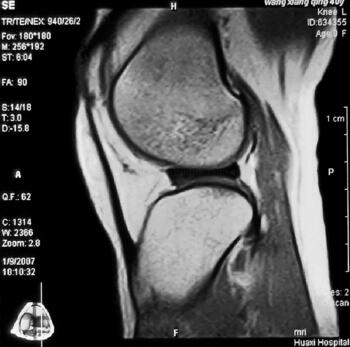

内侧半月板损伤图片(2)

核磁是目前为止,无创检查中,诊断半月板损伤 最准确的辅助检查手段